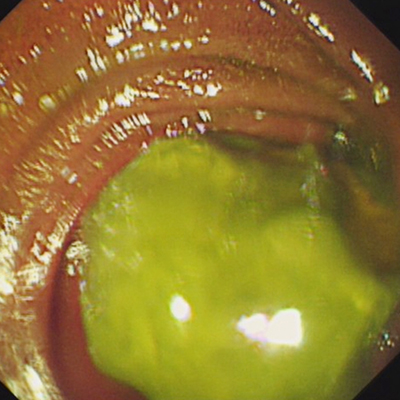

近日,我院消化內(nèi)科收治了一名“腸梗阻”的婆婆。經(jīng)檢查及多次詢問(wèn)患者,發(fā)現(xiàn)患者發(fā)病前曾經(jīng)吃了柿子及山楂等富含大量鞣酸的水果,而原本多發(fā)于胃內(nèi)的胃石,竟然進(jìn)入了空腸上段。醫(yī)生介紹,普通的胃鏡無(wú)法到達(dá)空腸上段,無(wú)法將“石頭”取出,如果無(wú)法經(jīng)內(nèi)鏡取石,婆婆就要到外科通過(guò)開(kāi)腹手術(shù)“取石”。經(jīng)科室專家反復(fù)討論,決定在沒(méi)有小腸鏡的情況下,運(yùn)用結(jié)腸鏡進(jìn)入空腸“取石”。

最終,內(nèi)鏡護(hù)士配合經(jīng)驗(yàn)豐富的內(nèi)鏡專家,經(jīng)過(guò)一個(gè)多小時(shí)的努力,幾經(jīng)周折終于將結(jié)腸鏡送達(dá)空腸,找到并順利將“石頭”取出。術(shù)后婆婆腹痛、腹脹好轉(zhuǎn),排便排氣正常,可以正常進(jìn)食。出院時(shí)婆婆向醫(yī)護(hù)人員豎起了大拇指,表達(dá)了她的感激之情。